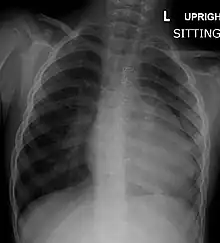

| Right ventricular hypertrophy | The right ventricle is more muscular than normal, causing a characteristic boot-shaped (coeur-en-sabot) appearance as seen by chest X-ray. Due to the misarrangement of the external ventricular septum, the right ventricular wall increases in size to deal with the increased obstruction to the right outflow tract. This feature is now generally agreed to be a secondary anomaly, as the level of hypertrophy tends to increase with age.[32] |

Before more sophisticated techniques became available, chest x-ray was the definitive method of diagnosis. The abnormal "coeur-en-sabot" (boot-like) appearance of a heart with tetralogy of Fallot is classically visible via chest x-ray, although most infants with tetralogy may not show this finding.[37] The boot like shape is due to the right ventricular hypertrophy present in TOF. Lung fields are often dark (absence of interstitial lung markings) due to decreased pulmonary blood flow.[15]: 171–72